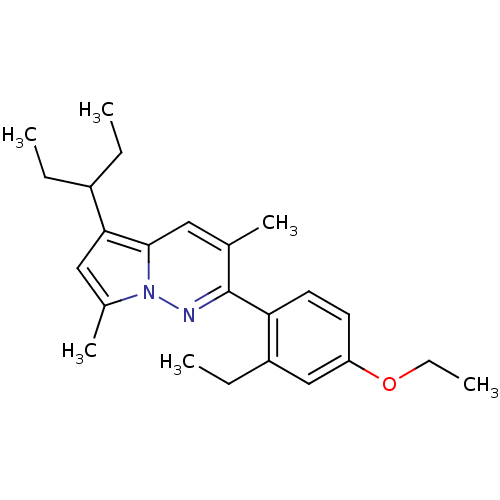

TargetCorticotropin-releasing factor receptor 1(Homo sapiens (Human))

Dupont Pharmaceuticals

Curated by ChEMBL

Dupont Pharmaceuticals

Curated by ChEMBL

Affinity DataEC50: 0.300nMAssay Description:Antagonist activity at human CRF1 receptor expressed in CHO-K1 cells assessed as CRF-stimulated cAMP accumulation by enzyme immunoassayMore data for this Ligand-Target Pair

Affinity DataEC50: 0.420nMAssay Description:Antagonist activity at CRF-R1 in mouse AtT-20 cells assessed as inhibition of human CRF induced cAMP accumulation after 30 mins by radioimmunoassayMore data for this Ligand-Target Pair

Affinity DataEC50: 0.440nMAssay Description:Antagonist activity at CRF-R1 in mouse AtT-20 cells assessed as inhibition of human CRF induced cAMP accumulation after 30 mins by radioimmunoassayMore data for this Ligand-Target Pair

Affinity DataEC50: 0.450nMAssay Description:Antagonist activity at CRF-R1 in mouse AtT-20 cells assessed as inhibition of human CRF induced cAMP accumulation after 30 mins by radioimmunoassayMore data for this Ligand-Target Pair